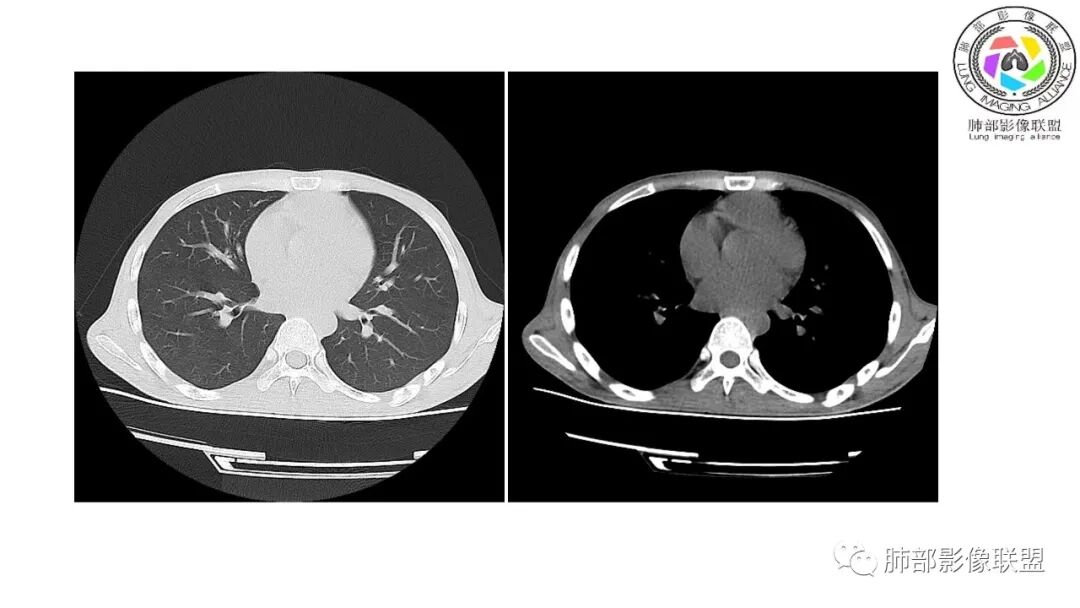

影像与临床:1.青年男性,HlV阳性,颜面部皮疹(未提供皮疹图像)、发热(高热),实验室CRP、PCT高,T-Spot阴性。2.右肺下叶空洞结节,壁厚不均,边界清楚,其内线状影,未见液平及钙化,未见卫星灶,纵隔淋巴结增大,双侧腋窝见增大淋巴结。心腔内低密度提示贫血可能。肝脾影增大,未见结节影及块影。腹膜后见多发增大淋巴结。

综合分析:本例肺部影像学改变并不具有特征性,空洞性病灶须与多种疾病鉴别,但年轻HIV阳性患者,高热,皮疹,肝脾增大,纵隔、腋窝、腹膜后见多发增大淋巴结等都强烈提示马尔尼菲篮状菌感染的可能性。